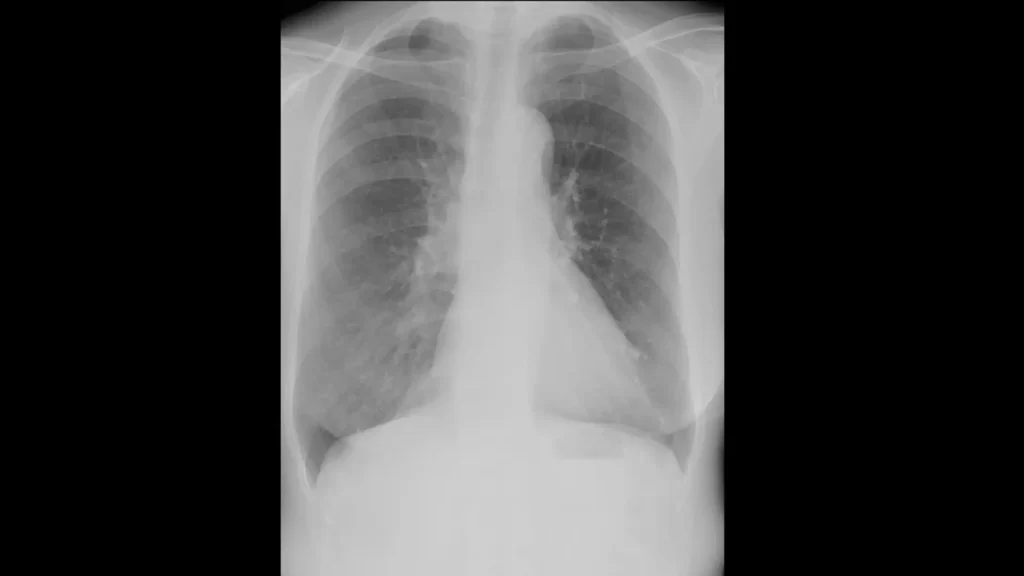

実際のCT画像所見

以下に

①:正常の肺

②:炎症の影

③:肺がん

④:③の患者さんのX線画像

を掲載します。

やはり、④のX線では肺がんを指摘するのは難しいですが、③でははっきり影がわかります。

ちなみにこの患者さんは、健診のX線では異常を指摘されませんでしたが、咳があったため心配で受診し、CTを撮ったところ肺がんが見つかりました。